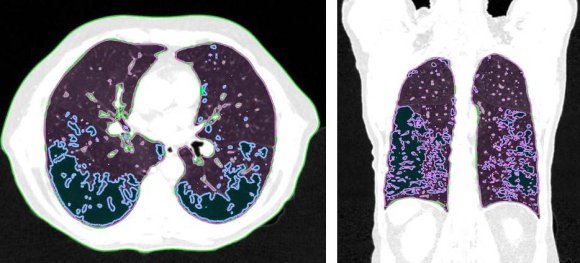

In patients with lung cancer who are candidates for radiotherapy treatment, densitometry provides additional information about the patient's clinical condition (14,15), in addition to the possibility of visually mapping the whole lung tissue and its different densities (figure 1).

All CT scans were examined for their lung density characteristics. Lung density measurements were made on radiotherapy planning CT scans, obtained with a 64-slice CT scanner (Ingenuity Core 64; Philips Healthcare, Cleveland, OH, USA). The structures of interest were outlined using the Eclipse radiotherapy planning system v15.6 (Varian Medical Systems, Palo Alto, CA, USA). The structures of interest were defined as "Right Lung," "Left Lung," and "Lungs" (both lungs drawn as a single structure) and automatically segmented, as were the structures corresponding to the different density ranges to be analyzed.

The structures corresponding to the attenuation ranges were obtained using the "Image Thresholding" tool (figure 2), which allows manual selection of HU values. They were defined as "Emphysema" for attenuation ranging from -1000 to -950 HU, "Normal Tissue" (functional lung volume) for attenuation ranging from -949 to -700 HU, and "Fibrosis" for attenuation ranging from -699 to -200 HU. The attenuation values of -949 HU and -699 HU were used to avoid data duplication. The volumes were then measured and recorded in a table. Given its importance in the clinical and oncological treatment of patients with lung cancer, emphysema was divided into three groups. Emphysema was considered insignificant when it involved less than 5% of the total lung volume, and severe emphysema was defined as involvement more significant than 15% (19). Fibrosis was considered a single group.